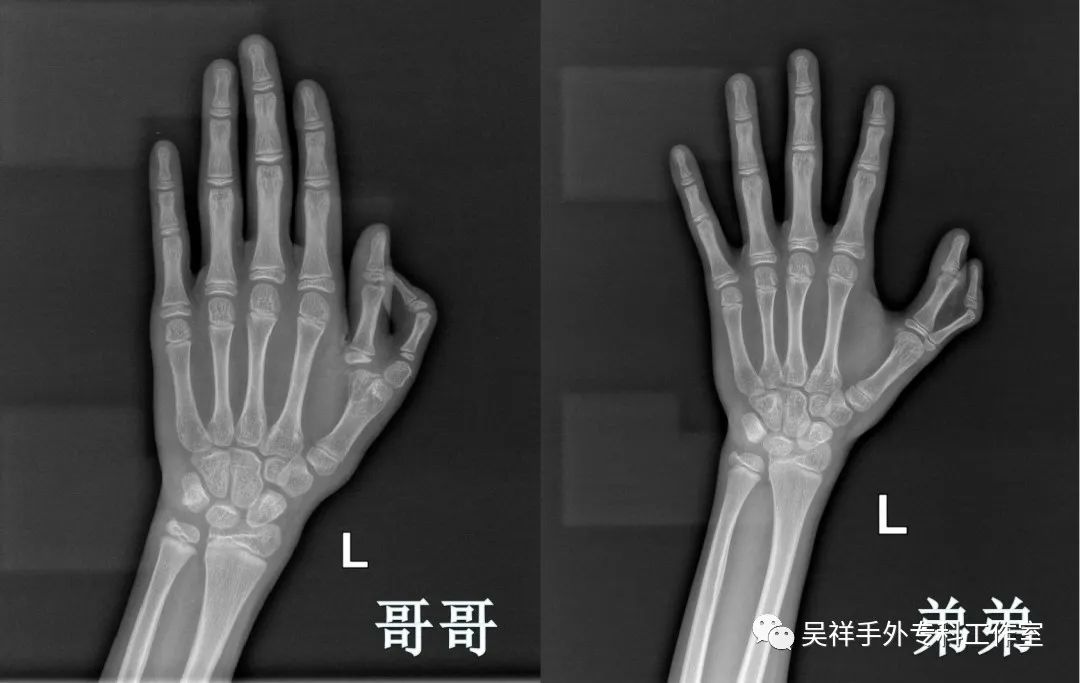

双胞胎兄弟术前X光片

检查发现,哥哥小华属于多指畸形Ⅶ型(三指节型),弟弟小明属于Ⅵ型(掌骨型)。“弟弟的手指畸形处理起来比较麻烦,因为两个指体共用一个掌骨,导致原本的拇指有些畸形,还需进一步矫正。”